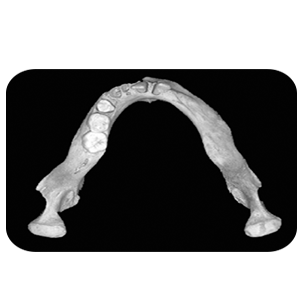

Units of the Department of Forensic Medicine and Clinical Toxicology Head of the Department's Message Services Units Academic Staff Course Description The department has the following devices and samples: